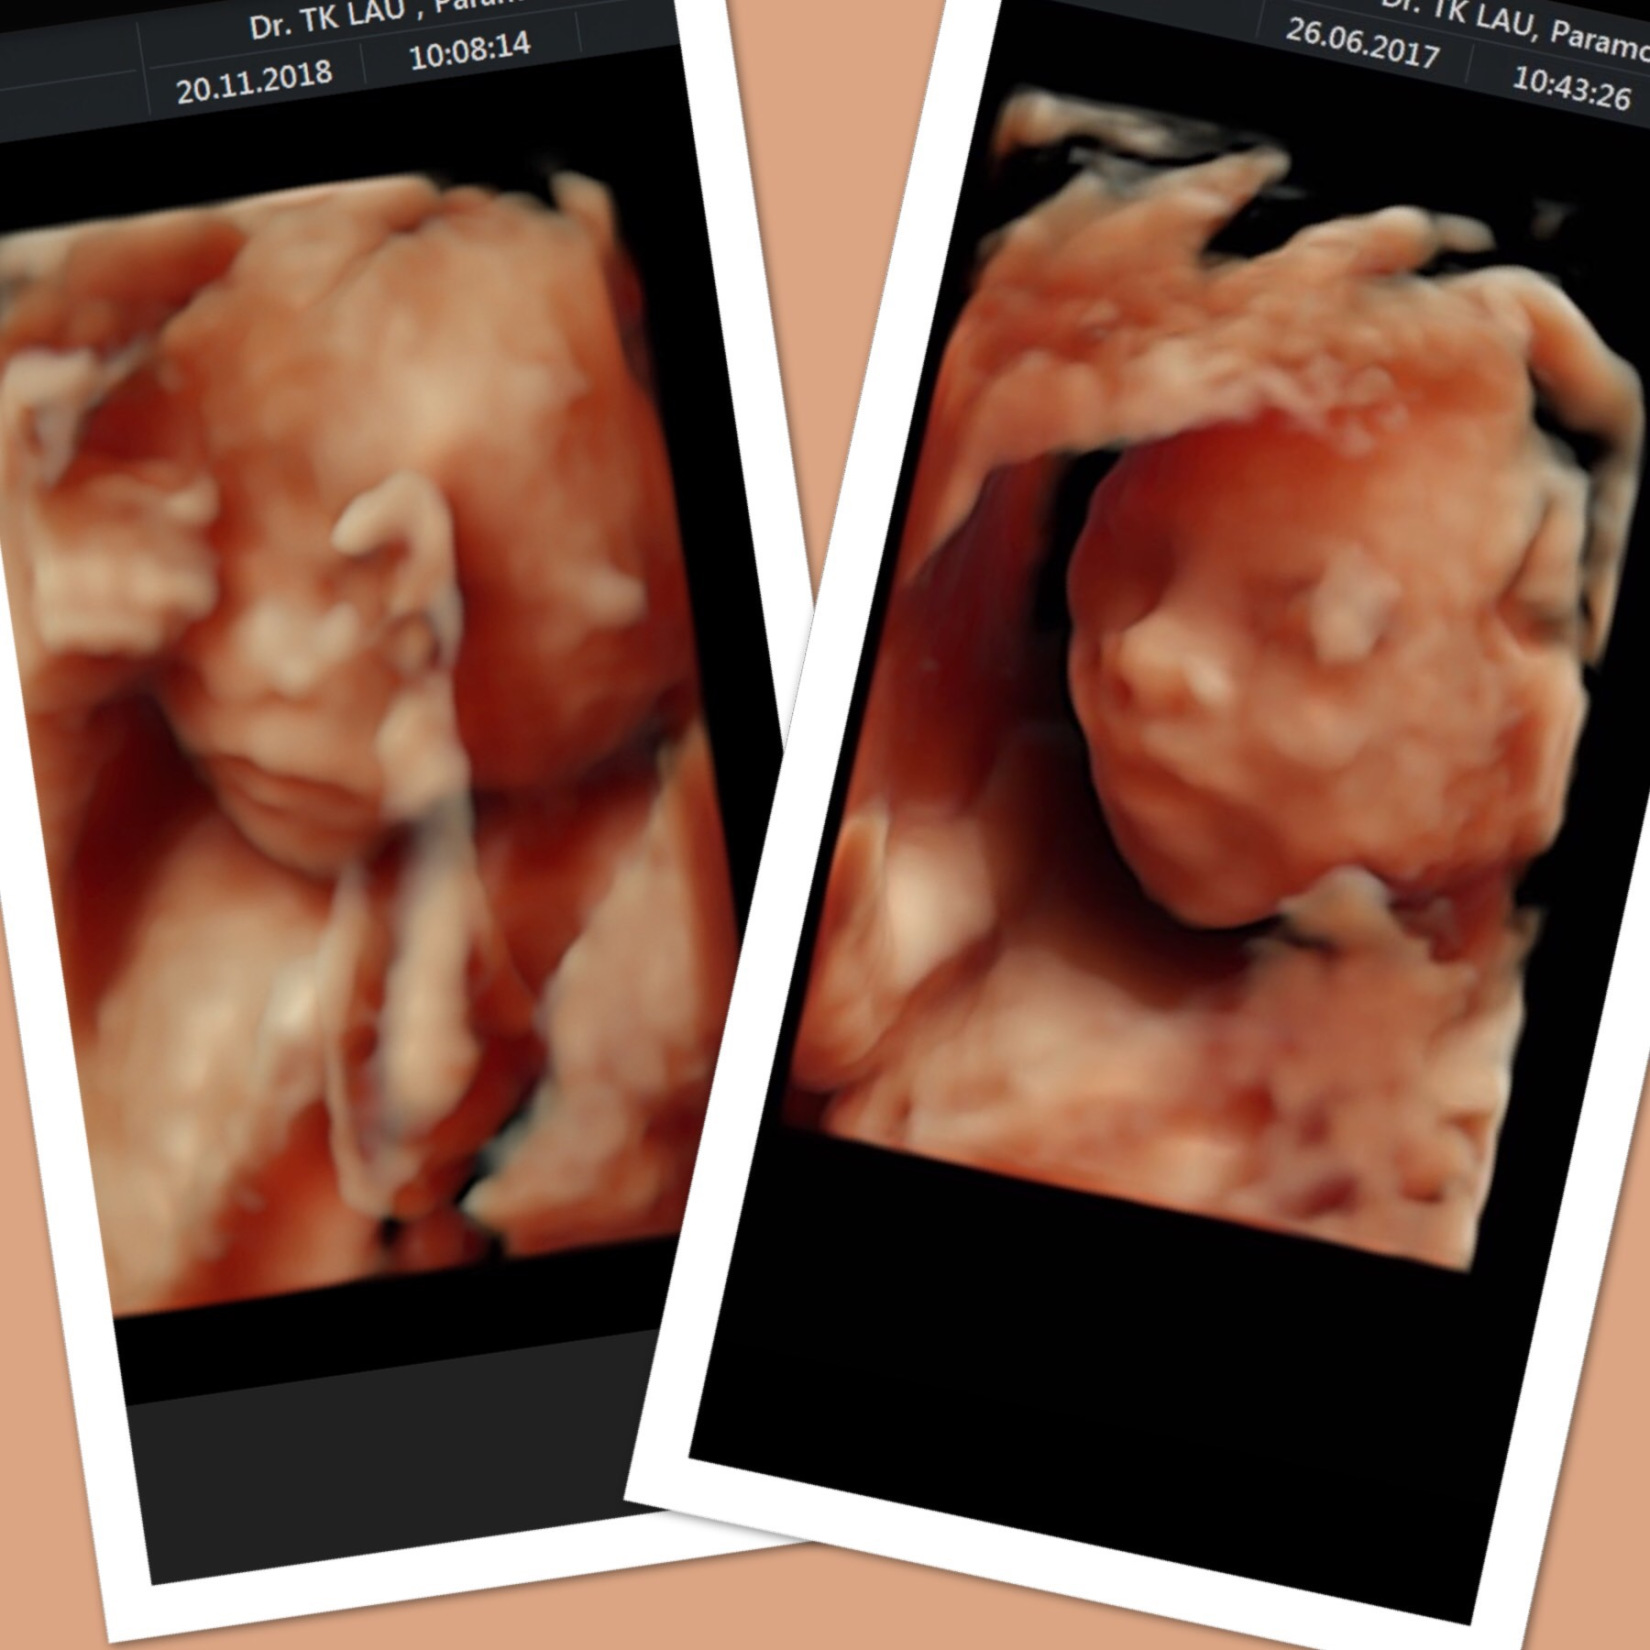

俾大家睇下我第一胎同第二胎既4D圖。其實我覺得兩個好似似樣。